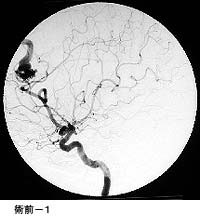

破裂脳動脈瘤に対するコイル塞栓術GODコイルだとちょっと古いので、コイル塞栓術とする方が良いのではないかと思います。

術後 コイルにより動脈瘤が写らなくなりました。